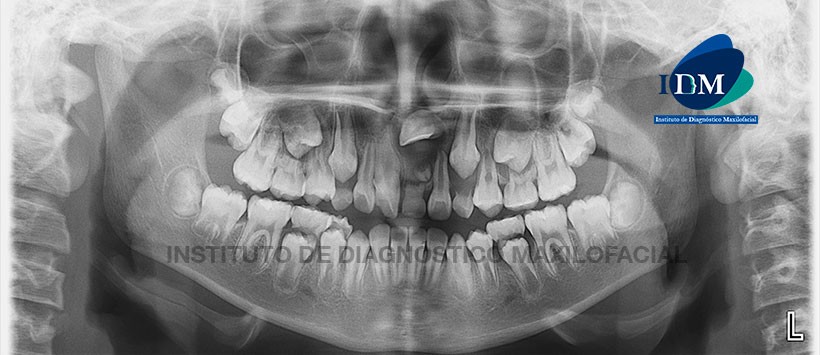

En la radiografía panorámica (Figura 1) se aprecia a la pieza 2.1 retenida en aparente posición mesioangular y con la corona proyectado a nivel de la espina nasal anterior; se visualiza una imagen radiolúcida pericoronal de límites definidos y bordes corticalizados asociado a la presencia de una pieza supernumeraria localizado en reborde alveolar y a la persistencia de la pieza 6.1.